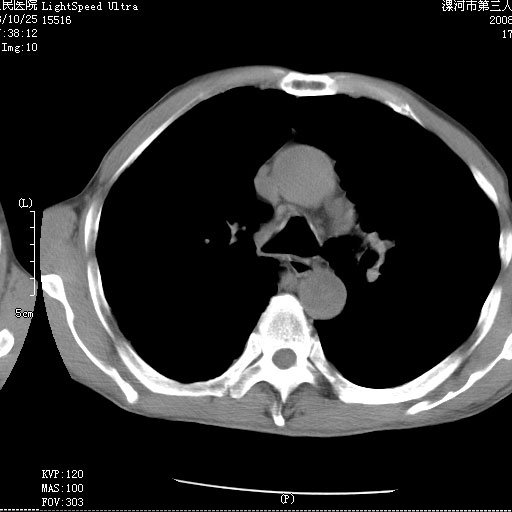

m 老年 发烧、呼吸困难,慢支、肺气肿多年;记的那次是下午大概17:38做的,晚上窒息死亡。

上面的层面就慢性支气管炎肺气肿、肺大泡,别的没有什么、也就不传了。

当时我怀疑:1、阻塞性肺不张早期 2、肺脓肿早期,望老师们发表意见

应该是脓胸的表现,右下肺气管阻塞考虑为痰栓.

你怀疑的有道理,慢支、肺气肿、肺打泡是有了,右下肺的病变有待商议;

首先考虑右下肺炎症并不张,不除外早期肺泡癌改变

病灶边缘清---多个含气小腔---近端未见通畅气管影-----支持-----慢性肺脓肿继发阻塞性肺不张

阻塞性肺不张原因-----脓液未排出

1、右侧脓胸;2、copd;

3、细支气管肺泡癌可以排除,病变以斜裂为界,呈大片状高密度影,内可见多发小气泡,表明有产气杆菌感染所致,内无明显的支气管“枯树枝征”表现,再结合其临床改变(细支气管肺泡癌临表表现重、影像表现轻)所以不符合细支气管肺泡癌(炎症型)的改变。

考虑为右肺下叶支气管痰栓形成并阻塞性肺不张及肺炎。

病变按肺叶分布,病变内可见多个小空腔影,未见充气支气管影,中间段支气管管腔肺窗示密度欠均匀,下肺支气管分叉处基底段支气管隐约可见,未见明显狭窄,中叶支气管通畅,

考虑:阻塞性肺炎伴小脓肿形成可能性大。(痰栓可能性大)

右下肺实变,内有弥漫分面小气泡而无支气管征,叶间裂前移,呈臌大之形,而无收缩之状,兼纵隔稍左行移,故。不支持不张,倒支持大叶肺叶,如楼上所说,小气泡不象残留之肺,不可以考虑产气菌感染吗。

阻塞性肺炎,肺脓肿形成。依据,右下支气管不通,大片实变形内可见小气泡。不支持肺不张。